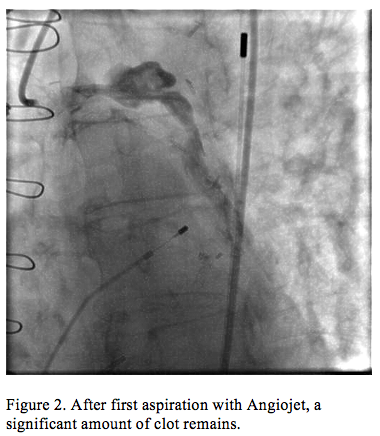

Cardiac catheterization revealed an occluded SVG to OM1 with TIMI flow 0 and possible thrombus (Figure 1, Video 1), a patent LIMA to LAD, an occluded stent within the SVG to Diagonal 1, and a patent SVG to RCA. A 0.014˝ x 135 cm Trailblazer catheter coronary guidewire engaged the SVG to OM1 graft and crossed the lesion. A temporary pacemaker and an intra-aortic balloon pump were placed due to bradycardia and hypotension. A 5 Fr Export catheter was then passed to the thrombus and approximately 15 mL of thrombus were aspirated. Repeat aspiration resulted in a collection of 20 mL of thrombus; however, a significant amount remained (Figure 2, Video 2). A 0.041" x 135 cm TrailBlazer catheter was then advanced to the thrombus and 8 mg of intracoronary abciximab were injected.

Improved flow (TIMI grade 2) was immediately seen, and a discrete lesion was apparent just proximal to the anastomosis of the SVG graft to OM1 artery (Figure 3). A VeriFLEX OTW bare-metal stent was deployed. After postdilatation and injection of 180 mcg intracoronary adenosine, there was TIMI grade 3 flow at the SVG to OM1 (Figure 4, Video 3), ST elevations nearly resolved, and the patient expressed immediate relief of chest pain. Intravenous abciximab was infused (10 mcg/min) for 12 hours postprocedure. Echocardiography the following day revealed severely decreased left ventricular systolic function (ejection fraction <25%) with akinetic inferior, posterior, and anterolateral walls.